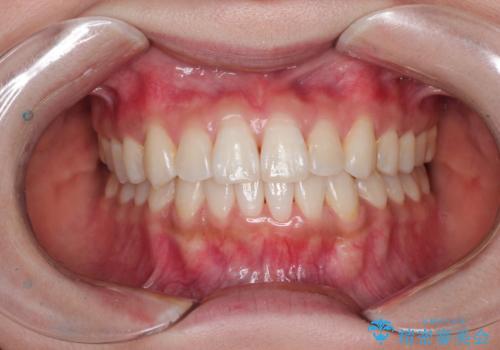

前歯のデコボコを改善 インビザライン矯正

担当医 藤巻太一朗